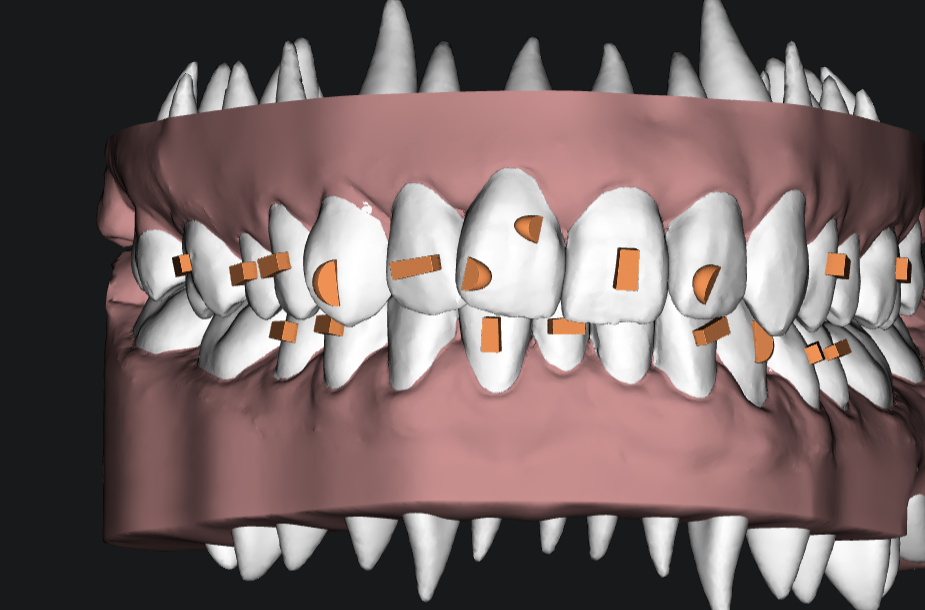

نقدم أحدث الحلول في تقنية التقويم الشفاف لضمان نتائج مبهرة وطبيعية.

تقنيات متطورة

تكنولوجيا متقدمة لراحتك

نستخدم أفضل المواد وأحدث التقنيات لرحلة علاج آمنة وفعالة.